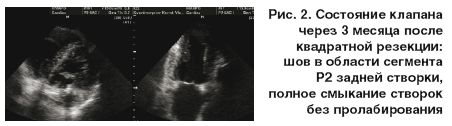

Повторная ЭхоКГ через 3 месяца (12.07.2006) выявила следующие изменения: регресс гипертрофии ЛЖ (индекс массы миокарда ЛЖ – 90 г/м2) с сокращением его полости на 7 мм и реверсией рестриктивного типа диастолической дисфункции, сокращение полости ЛП до 4,5 см, отсутствие признаков легочной гипертензии (расчетное систолическое давление в легочном стволе – 25 мм рт. ст.). В результате пластики МК в области сегмента Р2 четко визуализируется яркий эхогенный шов в области резецированного сегмента с небольшим ограничением подвижности задней створки. При этом патологических токов на МК не зафиксировано (рис. 2).